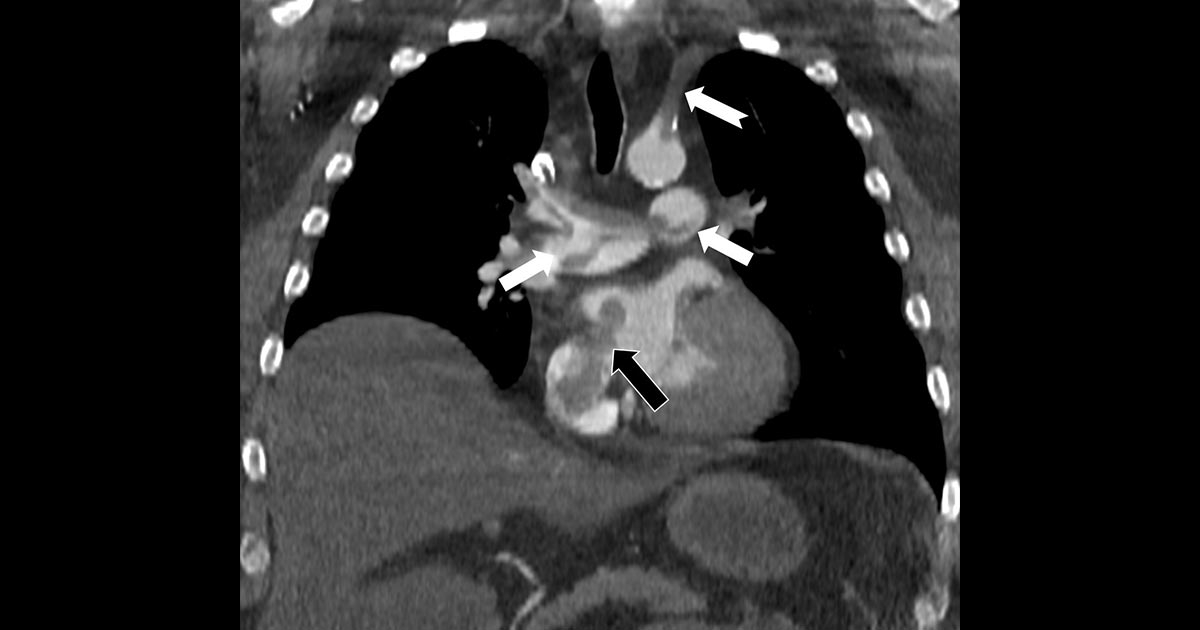

Bir dönem Özel Denizli Tekden Hastanesi’nde de görev yapan Prof. Dr. Nevzat Karabulut’un yaptığı çalışmada; akciğerin bilgisayarlı tomografi anjiyografisi sayesinde toplar damarlardan kaynaklanan pıhtının akciğer damarlarını tıkaması yanında, kalpteki delik nedeniyle kalbin sağ tarafından sol tarafına geçerek ana atardamara ulaştığı ve sol kol damarını tıkadığı gösterildi.

Emboli görüntülemesi konusunda çok sayıda bilimsel çalışması bulunan Prof. Dr. Karabulut, genelde bacak damarlarından kaynaklanan pıhtıların ölümcül olabilen akciğer embolisine yol açması yanında, kalp deliği olan hastalarda ana atardamar yoluyla beyin, kol ve bacak gibi vücudun diğer bölgelerine de geçerek ani damar tıkanmasına (paradoks emboli) bağlı bulgulara yol açtığını belirtti. Prof. Dr. Karabulut’un çalışmasında nedeni bilinmeyen pıhtı atmalarında kalpteki gizli deliklerin mutlaka araştırılması gerektiği vurgulanarak ekokardiyografi ve bilgisayarlı tomografi tetkiklerinin erken ve doğru tanı koymada hayat kurtarıcı rolüne dikkat çekildi.